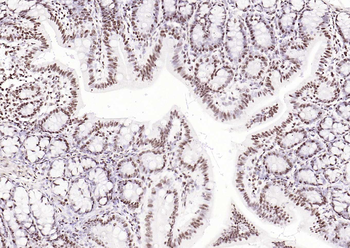

Phospho-Smad3 (Ser423 + Ser425) Rabbit Polyclonal Antibody [orb6983]

FC, IF, IHC-Fr, IHC-P, WB

Bovine, Canine, Equine, Gallus

Human, Mouse, Porcine, Rat

Rabbit

Polyclonal

Unconjugated

100 μl, 200 μl, 50 μlPhospho-SMAD5 (Ser463 + Ser465) Recombinant Rabbit Monoclonal Antibody [orb559123]